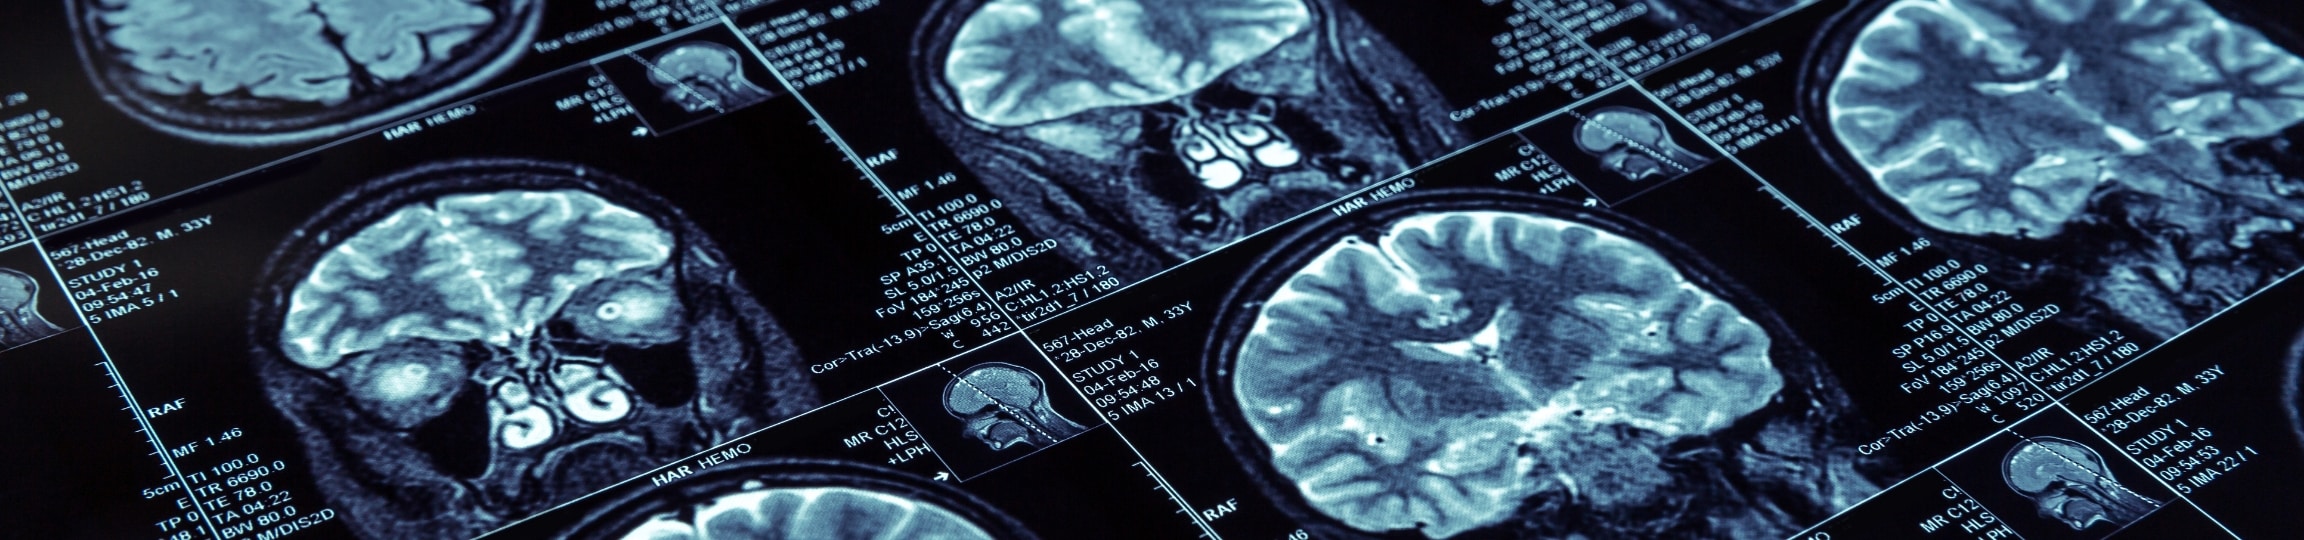

Access Wellness Healthcare

BrainScope Media